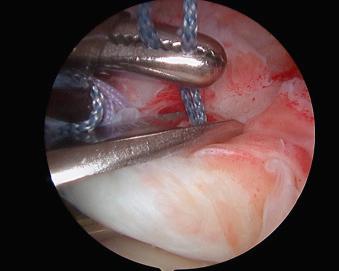

Straight medial retraction or retraction in an elliptical shape is the most common finding. As the tear size increases, the surgeon is less able to appreciate tear geometry. In the right shoulder, reverse L -shaped tears with a longitudinal component along the rotator interval allow the tear to rotate posteriorly. L -shaped tears have a longitudinal limb posteriorly, often at the junction of the supraspinatus and infraspinatus, in addition to the lateral, transverse detachment at the greater tuberosity ( Figs. 12.32–12.36 ). Longitudinal tears may occur in the area of the rotator interval and occasionally within the substance of the supraspinatus.

FIGURE 12.32, L -shaped tear.

FIGURE 12.33, L -shaped tear.

FIGURE 12.34, Reverse L -shaped tear.

FIGURE 12.35, Reverse L -shaped tear.

FIGURE 12.36, Reverse L -shaped tear repair.